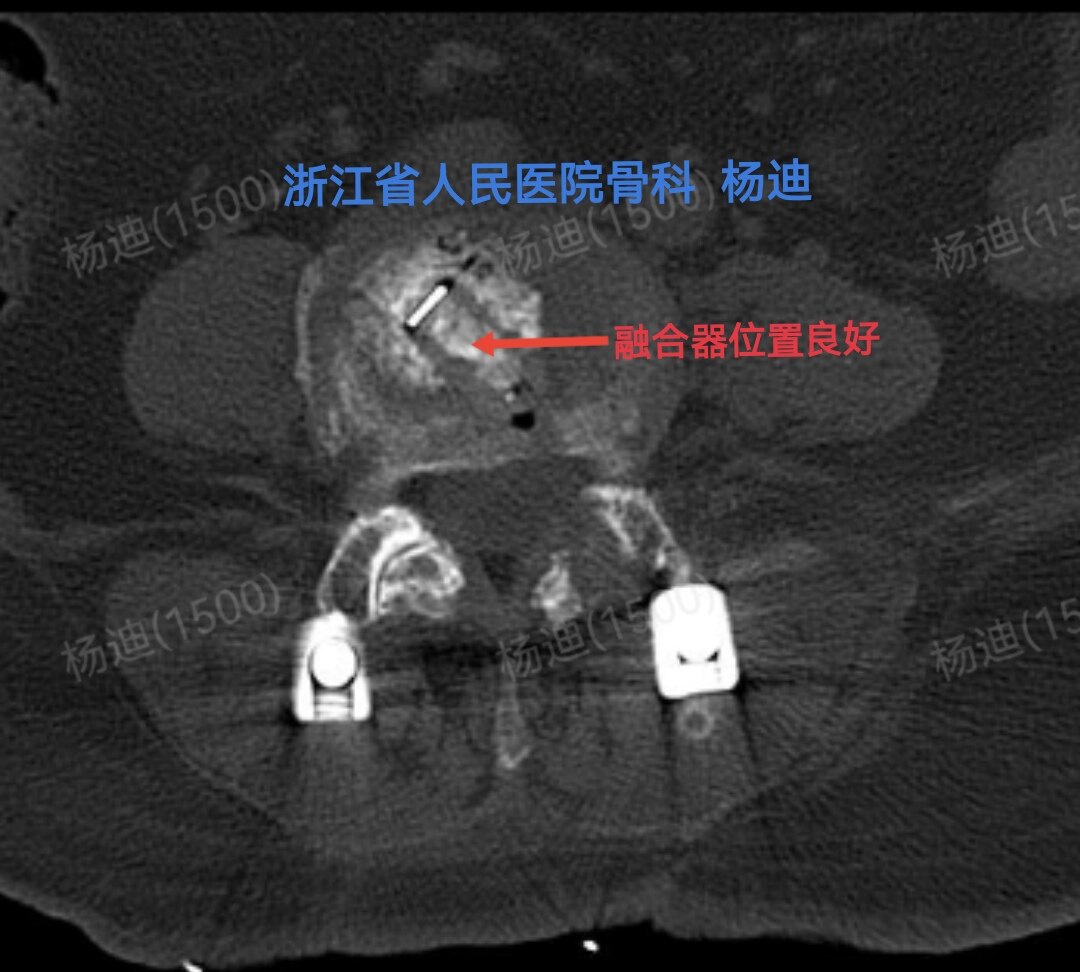

图为术后腰椎CT横断面,提示腰4/5间隙融合器位置及长度满意(红色箭头)。

CT冠状位重建:椎间高度恢复(橙直线间距离),融合器位置良好植骨充分(红箭头),螺钉位置良好(黄圈)